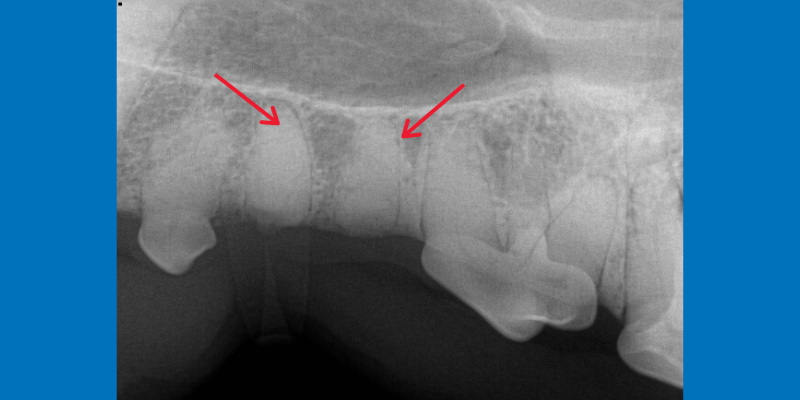

Maxillary premolar in a dog. The tooth looks normal upon visual exam, but dental x-rays reveal a missing tooth root (red arrows).